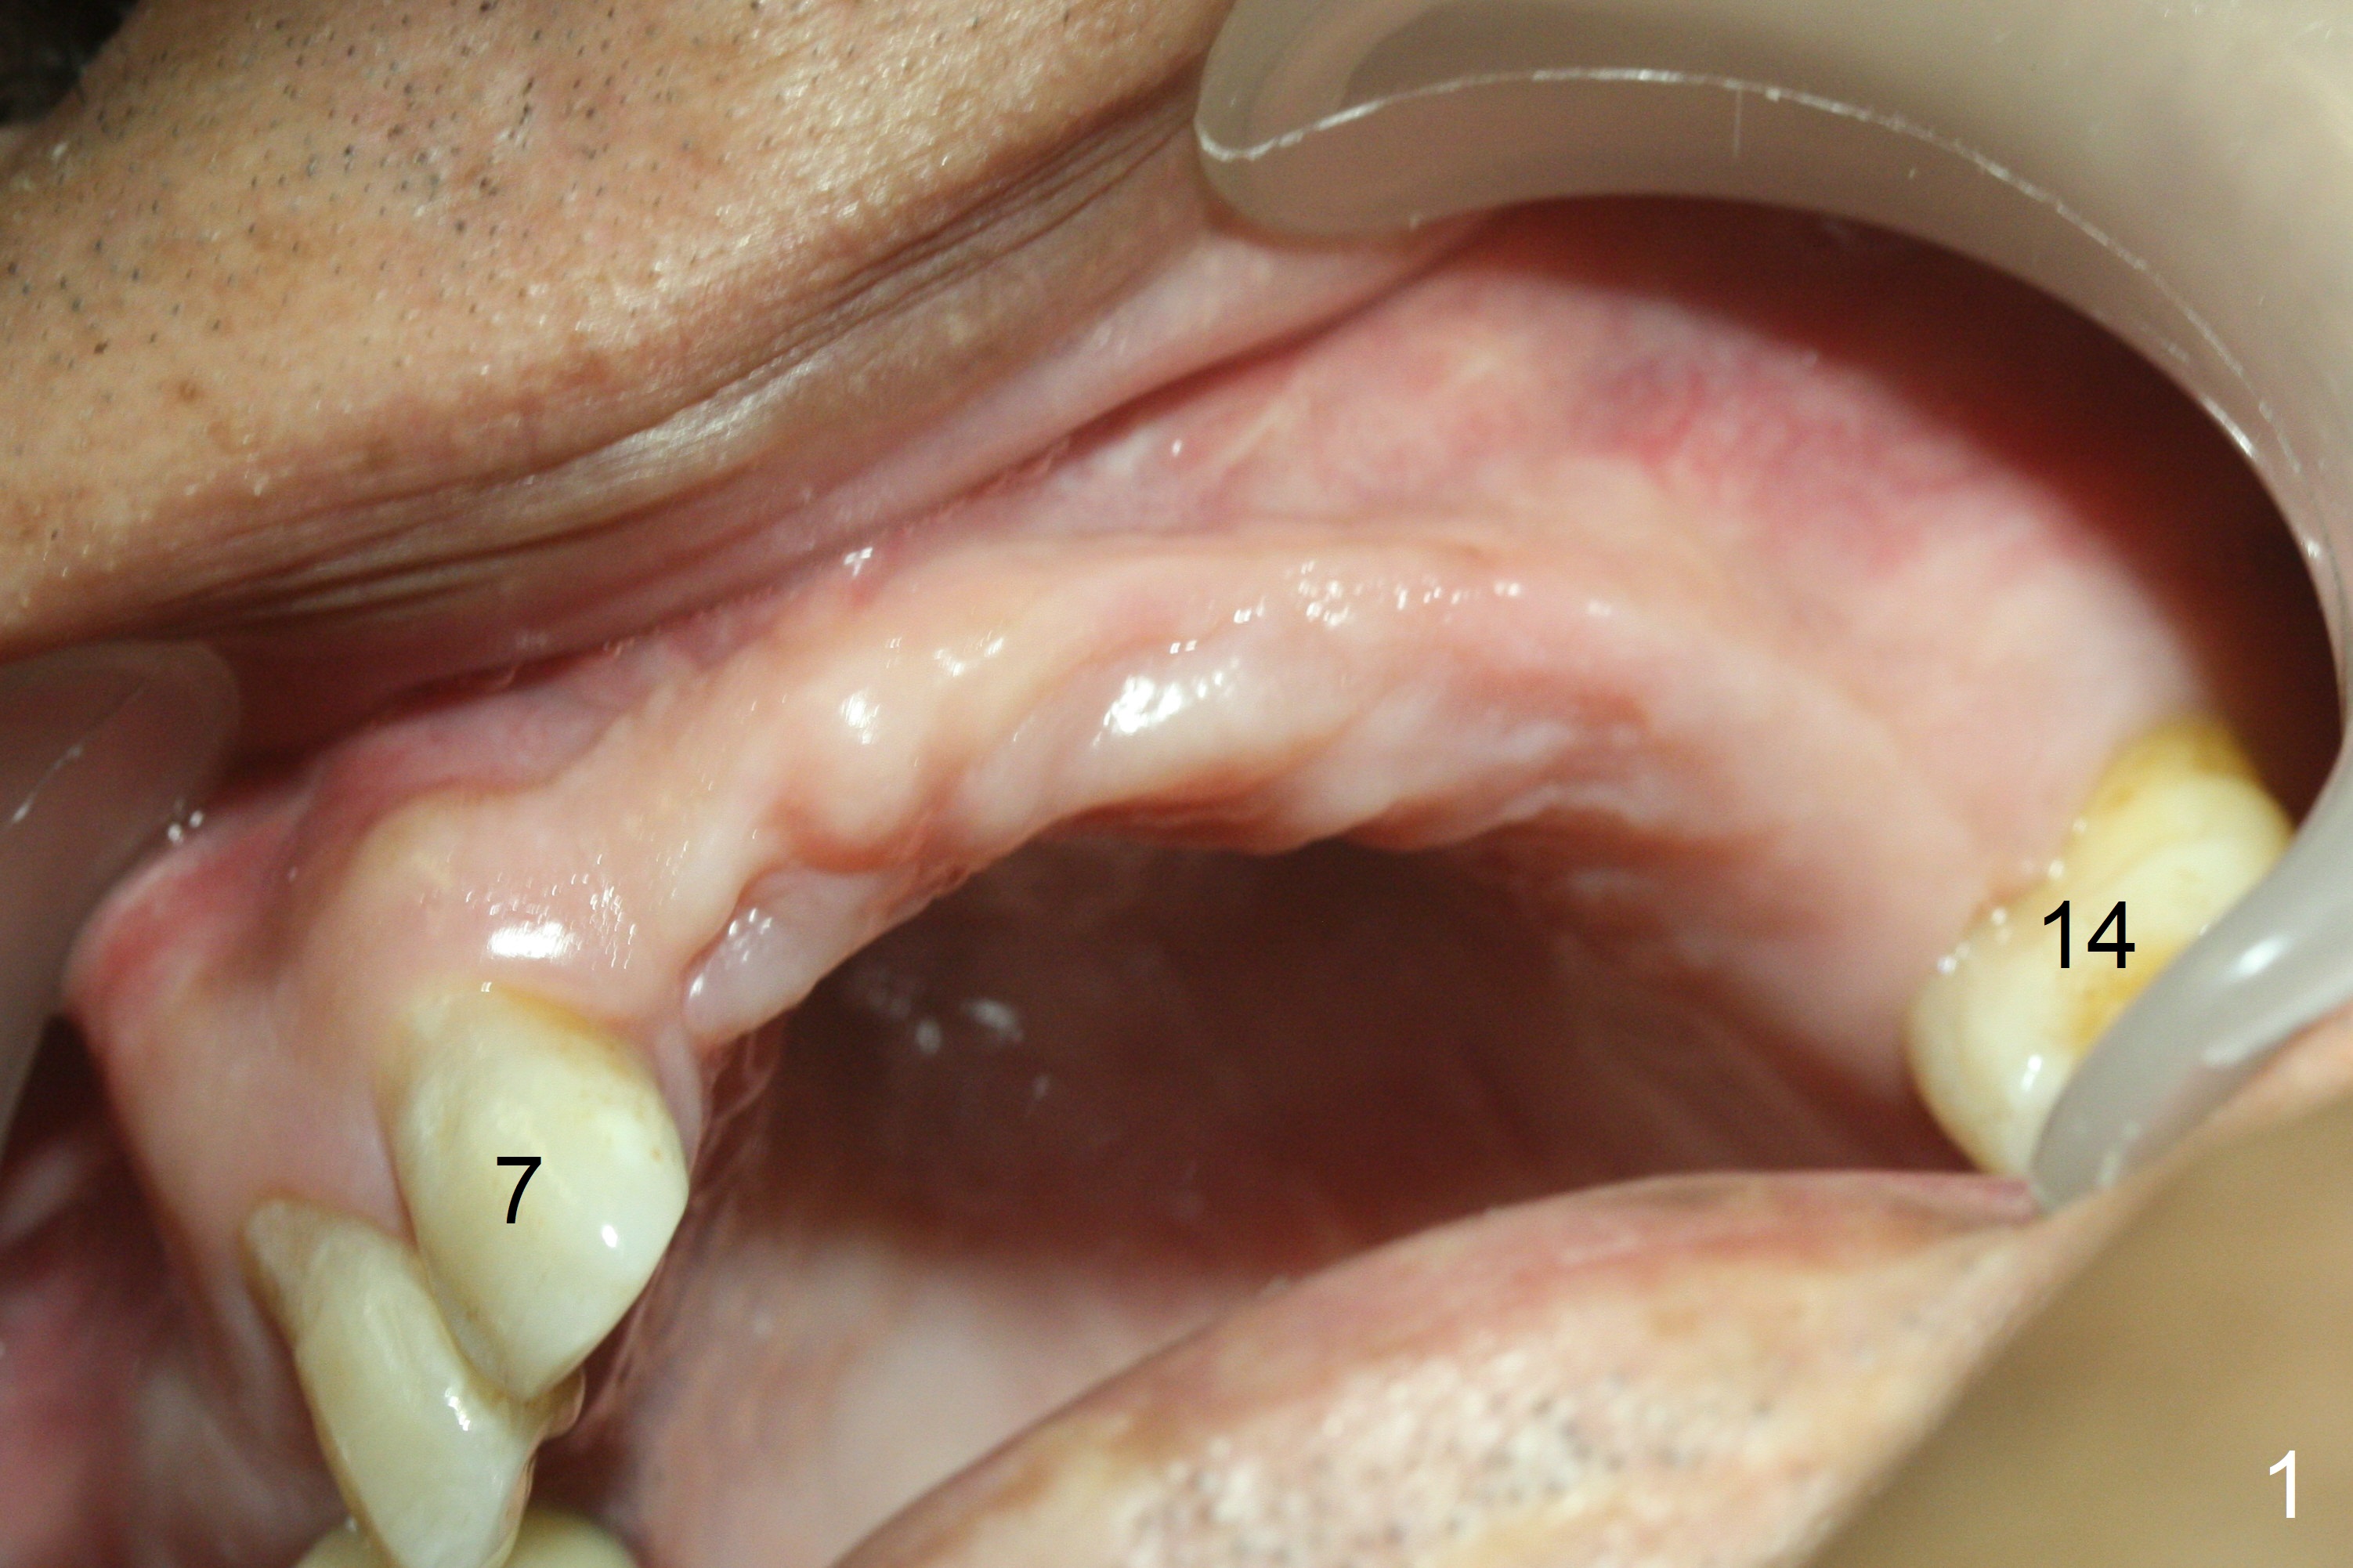

Fig.1: Narrow Ridge at #8 and 13.